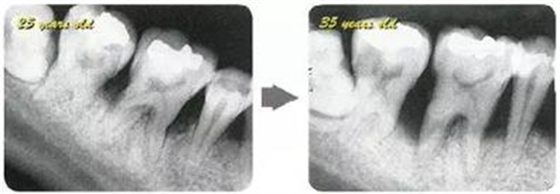

牙周病的發(fā)展因部位不同而發(fā)展程度不同的。10點(diǎn)后的狀態(tài)參考病例①和參考病例②的磨牙處的狀態(tài)相比較,思考下沒接受治療病情發(fā)展的特別性吧。

參考病例① 35歲女性

在左下第一磨牙在25歲時(shí)近中處可以看到垂直性的骨吸收,但35歲時(shí)吸收停止,原本沒有見到的遠(yuǎn)中處骨吸收的,現(xiàn)在卻吸收得很嚴(yán)重。

在右下處,原本有大量骨吸收的第一磨牙處的吸收卻變緩慢,原本沒有吸收的第二前磨牙卻出現(xiàn)了吸收。出現(xiàn)吸收的左上第一磨牙的遠(yuǎn)中處,吸收得越來越多了。

把10年間的變化做成表格。牙周病的發(fā)展根據(jù)各個(gè)人會(huì)不同,即使通一個(gè)人,不同牙齒,不同牙面發(fā)展的狀態(tài)也不同。